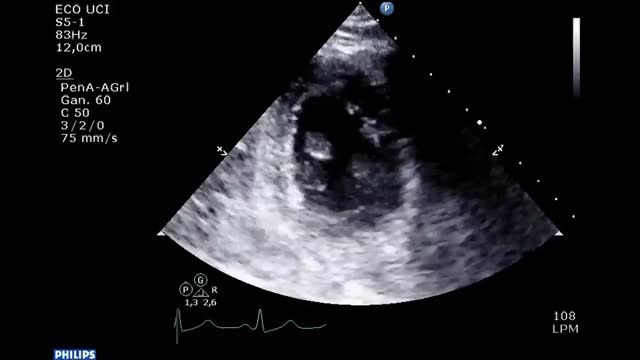

Pericardial tamponadeLeads to right ventricle collapse and decrease of RV output and by consequence LV output. From a subcostal view, we can assess the presence of pericardial effusion, which compromises the functionality of the heart. In a basic analysis of shock, the existence of severe effusion (>2 cm), collapse of the cavities in their respective diastoles, dilation of the Inferior Vena Cava with absence of respiratory variations and in some situations, visualisation on the two-dimensional TTE of “Swinging heart” which is associated to a large pericardial effusion testifies often cardiac tamponade.17

Some of the parameters assessed during basic echocardiography although not very sensitive, together with the medical history and clinical examination may raise suspicion of hypovolemia as a main cause of shock. The most frequently assessed by intensivists are: kissing walls of the LV which is a collapse of the walls of the LV during systole and the reduced left ventricular end-diastolic area (Video 4).